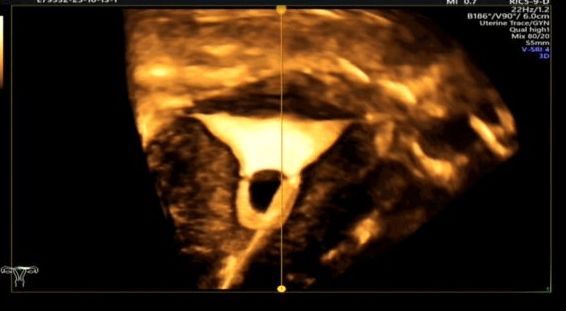

简单来说,这是一项评估输卵管通畅性的医学影像检查技术。检查时,医生会在宫腔内放置一根双腔造影管,通过推注造影剂,动态观察造影剂在宫腔、输卵管和盆腔的流动、积聚和弥散情况,从而判断输卵管的通畅度、走形以及病灶部位。通过这个快速安全的检查,输卵管的许多问题便能一目了然。

单角子宫合并右侧残角

子宫内膜息肉